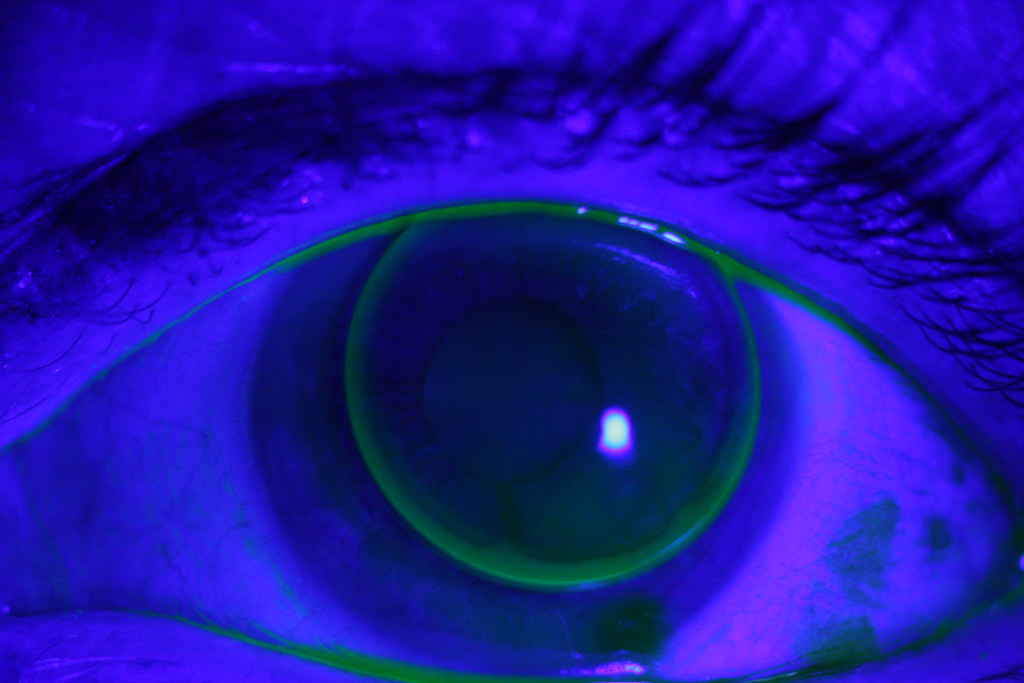

From webeye.ophth.uiowa.edu

Scratched Scleral Rigid Gas Permeable (RGP) Lens Can Rgp Lenses Damage Eyes Improving eyesight if you have keratoconus often involves wearing contact lenses. However, many wearers inadvertently make mistakes. Rpg contacts are better at retaining their shape and position in the eye than soft contact lenses, which makes them a better option if you’re suffering from keratoconus. Understanding and properly managing scleral and rgp contact lenses is crucial for optimal eye health. Can Rgp Lenses Damage Eyes.